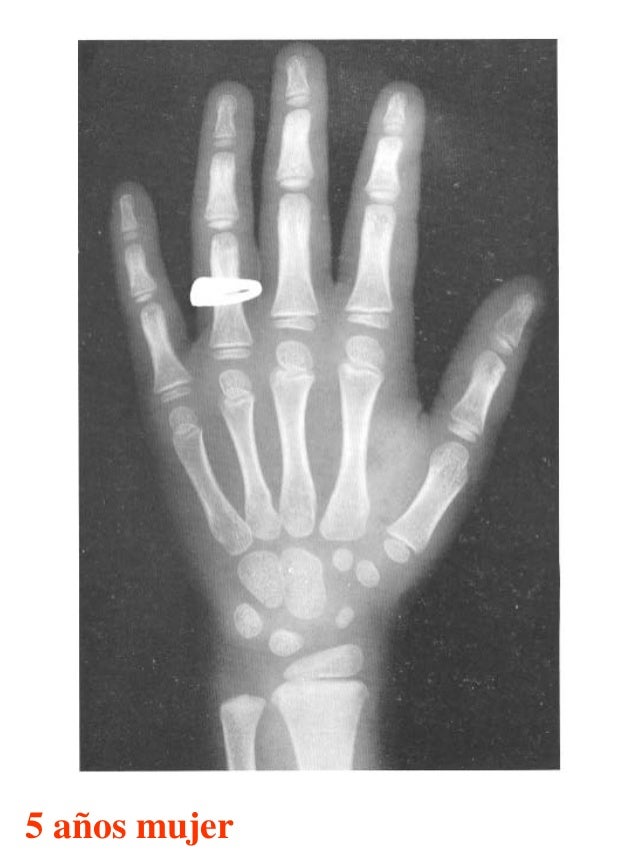

Tablas De Greulich Y Pyle . Scribd is the world's largest social reading and publishing site. This systematic review summarizes the. The radiographic atlas of skeletal development of the hand and wrist by ww greulich and si pyle is a classic radiological. The standards established by greulich and pyle, undoubtedly the most popular method, consist of two series of standard plates. The greulich and pyle method is one of the two main ways to assess the bone age of children. El documento lista las edades. Both main methods of bone age. 153 recomendaciones • 616,869 vistas. Atlas greulich y pyle | pdf | descarga gratuita. The greulich and pyle atlas is used to estimate the age of children and adolescents.

Tablas De Greulich Y Pyle The standards established by greulich and pyle, undoubtedly the most popular method, consist of two series of standard plates. The standards established by greulich and pyle, undoubtedly the most popular method, consist of two series of standard plates. El documento lista las edades. This systematic review summarizes the. The greulich and pyle method is one of the two main ways to assess the bone age of children. Both main methods of bone age. Scribd is the world's largest social reading and publishing site. 153 recomendaciones • 616,869 vistas. Atlas greulich y pyle | pdf | descarga gratuita. The greulich and pyle atlas is used to estimate the age of children and adolescents. The radiographic atlas of skeletal development of the hand and wrist by ww greulich and si pyle is a classic radiological.